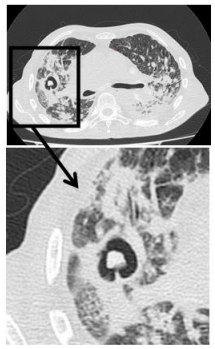

A seguir, está a imagem da tomografia computadorizada realizada.

O laudo da tomografia computadorizada do tórax foi: derrame pleural laminar bilateralmente. Sinais de enfisema centrolobular Cavitações de paredes espessadas no pulmão direito, uma delas apresentando formação nodular com densidade de partes moles no seu interior, medindo cerca de 1,1 x 0,9 cm, de aspecto pouco específico. Múltiplas opacidades centrolobulares esparsas por ambos os pulmões, assumindo configuração com aspecto de árvore em brotamento bilateralmente, associados a opacidades em vidro fosco na sua adjacência. Dentre os diagnósticos diferenciais deve-se considerar a possibilidade de processo infeccioso específico em atividade Espessamento difuso das paredes brônquicas. Traqueia e brônquios-fonte pérvios. Linfonodos proeminentes mediastinais e hilares, muitos calcificados. Aorta de calibre preservado. Calcificações vasculares. Coração de dimensões aumentadas.

Com base nas informações acima, e considerando as doenças mais prevalentes na população de rua no Brasil, as principais hipóteses diagnósticas seriam